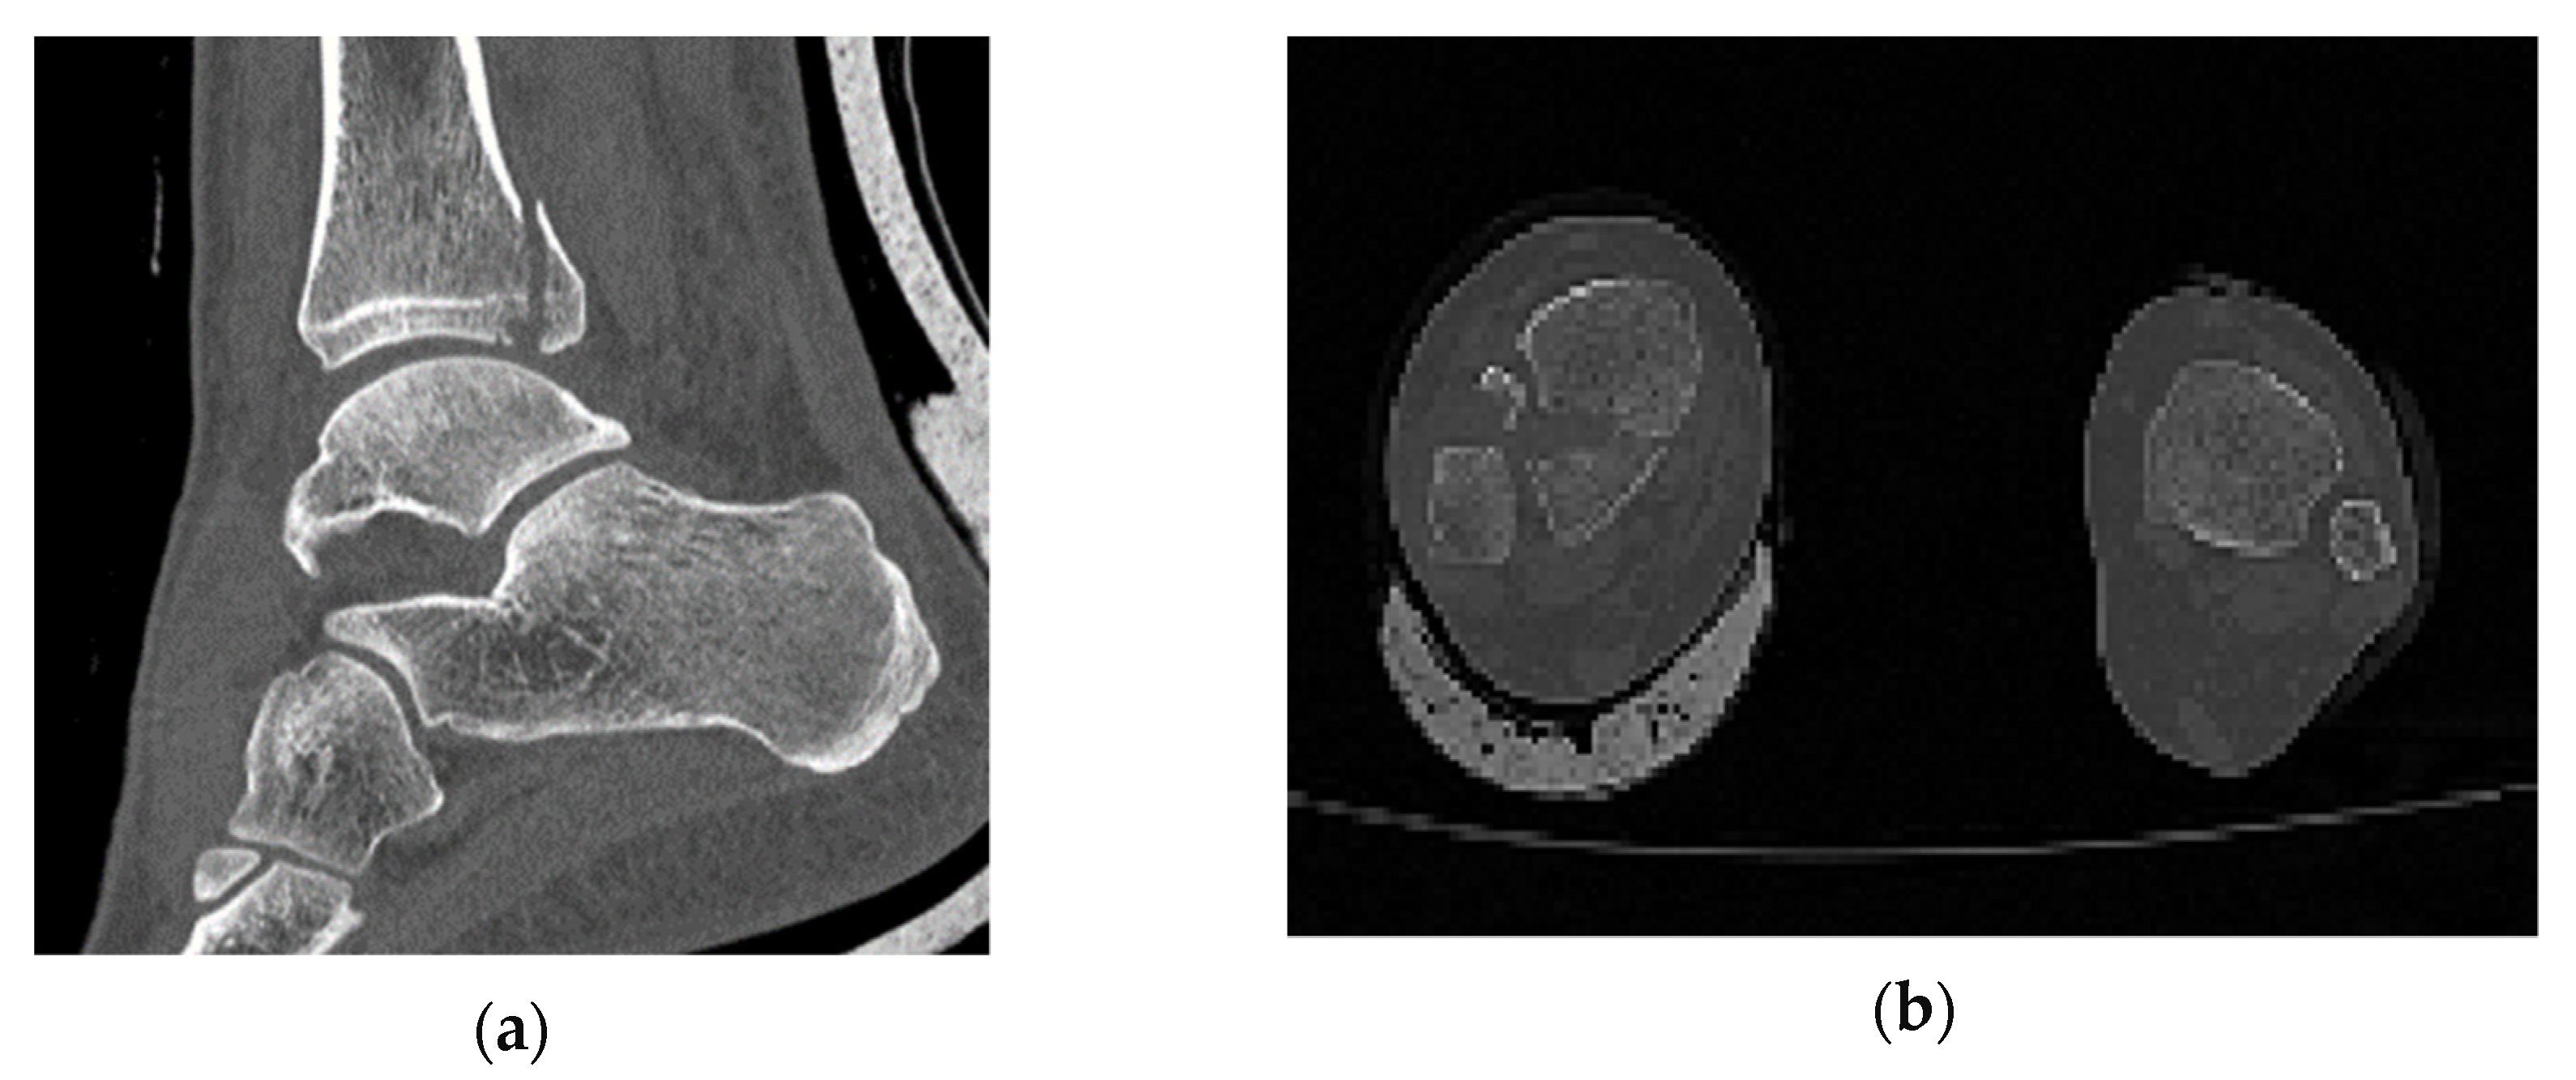

In comparison with industrial models, which are studied through computational methods, in biomechanics the object is not designed with a CAD software and its geometry varies randomly from person to person. In order to identify that the one and only fracture is the posterior malleolus fracture, all the ankle joint parts were thoroughly observed. The software RETOMO, as a tool, gave us the opportunity to run a 3D view around the CT scan and focus further on the fracture location. In practice, the tree dimensional image is recognized through the software and converted in a surface within the boundaries that the image defines. Afterwards, the surface is meshed and replaced with face elements. The first indication that the fracture is posterior malleolus, is given as when only the tibia has a broken part and the fibula appears complete (Figure 1). A second verification is that no fracture appears on medial malleolus.

Figure 1.

(a) Section cut of the posterior malleolus fracture; (b) plan view (fracture shown on the left).